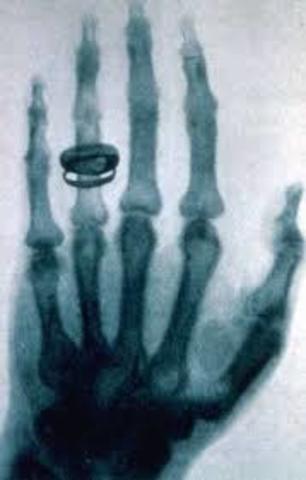

• X- radiation aka X-ray

X- radiation aka X-ray

Professor Wilhelm Roentgen discovering the X-ray in 1895. He was in his laboratory working with a cathode-ray when he observe a fluorescent glow of crystal on a table near his tube. He covered the tube with a heavy black paper and discovered a green colored fluorescent light generated. Roentgen found that the new ray could pass through most substances, including human tissue but not bone or medal.